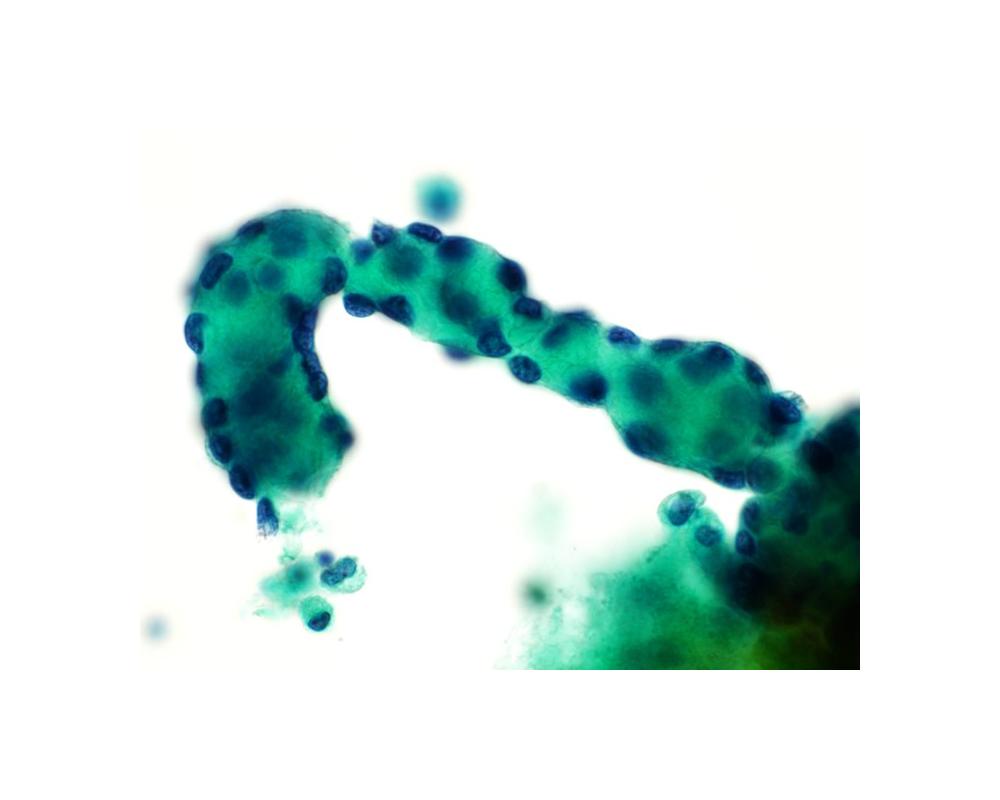

第38回日本臨床細胞学会九州連合会学会(熊本)スライドカンファレンス症例5

種別:体腔液

出題:和田 純平 大分県立病院臨床検査科病理部

| 年齢 | 50代 | 性別 | 女性 |

| 採取部位 | 胸水 | 採取方法 | 穿刺 |

既往歴:10年以上前に、腹部腫瘍の手術歴がある。

現病歴:X-10年に、胸水貯留の精査過程で腫瘍が認められ、現在まで化学療法を継続中である。直近の、胸水穿

刺吸引検体より作製された標本を提示する。

| 正解 | 5.高分化乳頭状中皮腫 |

▼選択肢及び投票結果

| 1.反応性中皮過形成 | 25件 | (24.0%) | |

| 2.腺癌 | 18件 | (17.3%) | |

| 3.扁平上皮癌 | 0件 | (0.0%) | |

| 4.上皮型悪性中皮腫 | 30件 | (28.8%) | |

| 5.高分化乳頭状中皮腫 | 31件 | (29.8%) | |

| 投票総数 | 104件 | (100%) |